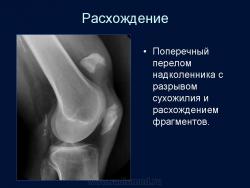

Фрагмент из прекрасной презентации Анатолия Владимировича Шумакова.